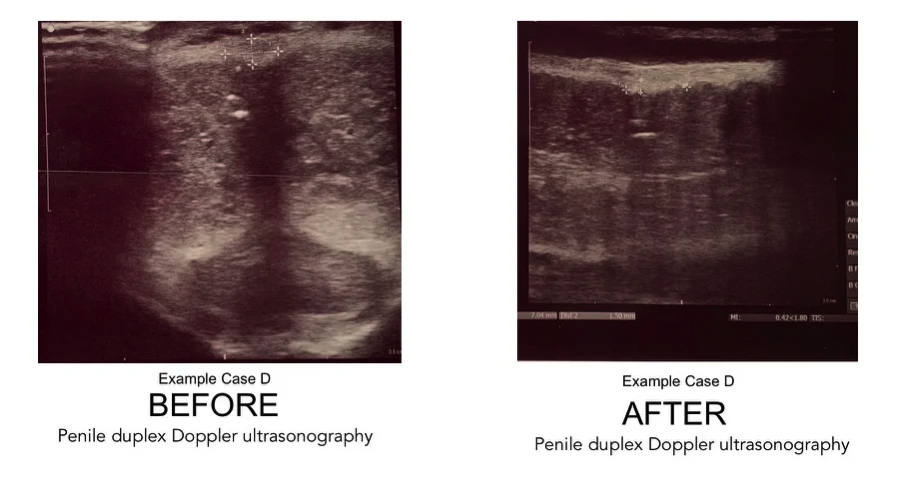

Highlights: Calcified Plaque Before & After Sonogram Images

Following is a set of four "before and after" duplex sonogram images of Peyronie's patients with calcified plaques